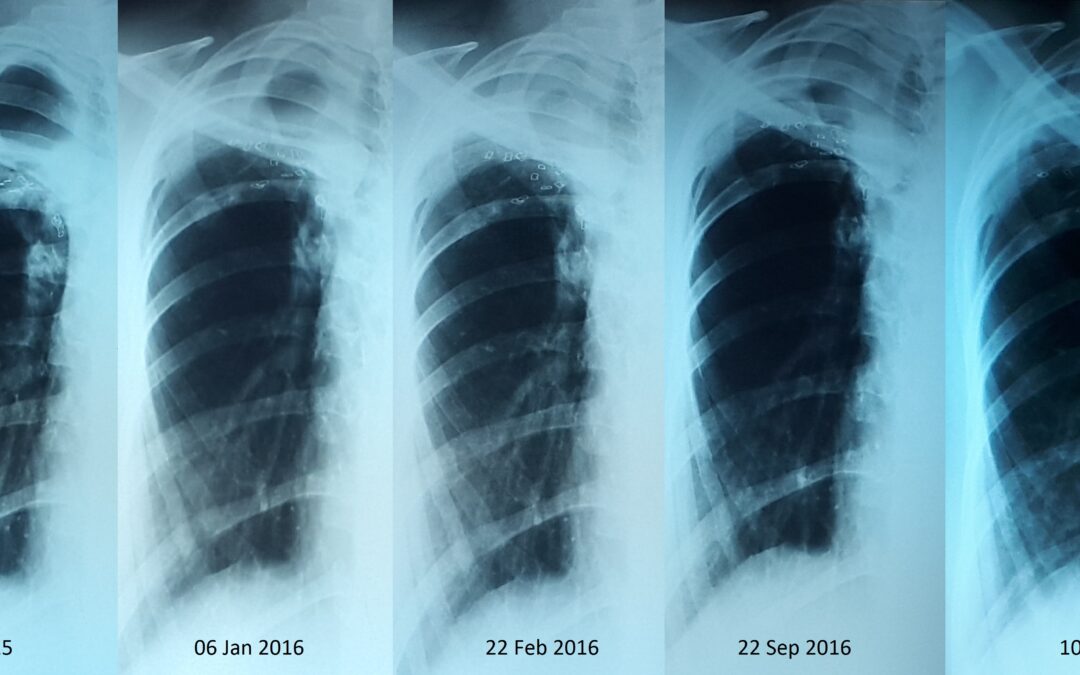

Трахеобронхиальное стентирование, рубцовый стеноз левого главного бронха. Пациент 49 летний мужчина. В 2007 году он лечился по поводу туберкулеза легких. В 2015 году — релапс. В течении многих лет у пациента одышка, возростаюшаяся недостаточность дыхания, из за...